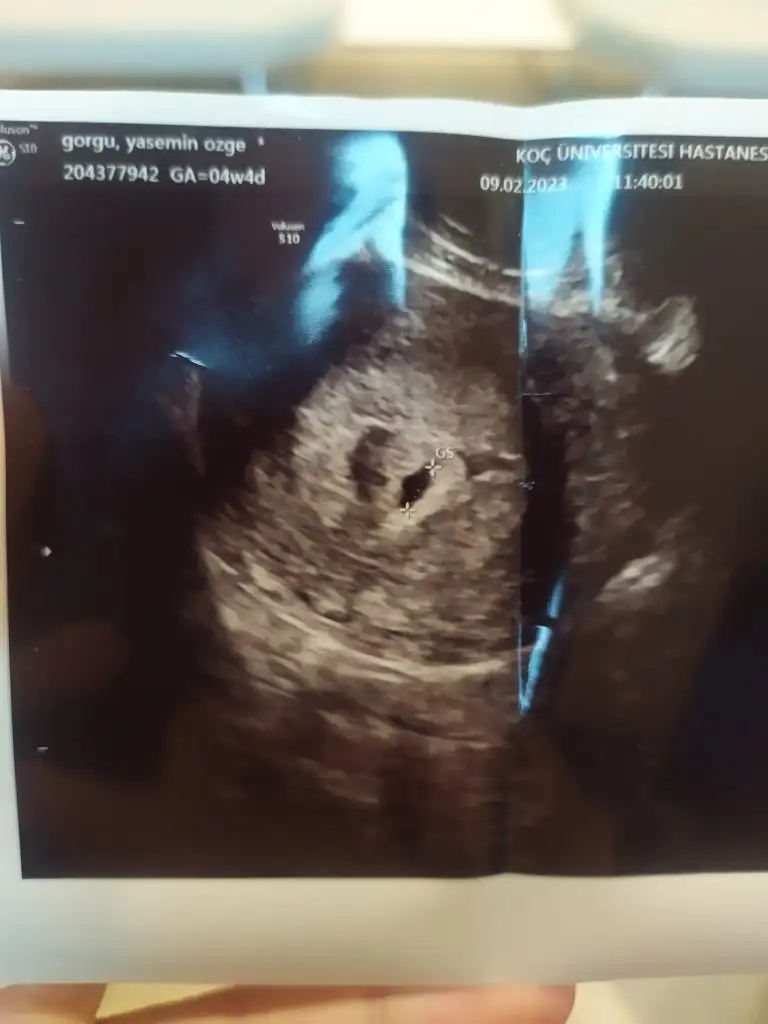

Kızlar selam size ne soracağım 10 gün önceki muayenemde vajinal ultrasonda bebek 6+1 çıkmıştı dün doktora gittik karından ultrasonla baktı 6 haftalık dedi ben anlamadım nasıl bişey 10 gün önce 6 haftalık olan çocuk 10 gün sonra nasıl yine 6 haftalık oluyor

Teşekkür ederimmm💕 vajinal muayene ile karından farkeder dedi daha çok ufak dedi o kadar son adet tarihim 13 kasım ama tüp bebekle hamile kaldım ben 26 kasım yumurta toplama 29 kasım transferim oldu canım

Canım lütfen üzülme. Daha çok yeni oluşuyor. Daha içinde bebek görünecek kadar büyümemiştir. Hem ben baktım senin kese fasulye gibi, bu erkek olacak anlamına geliyor (öyle derler ya)😊 Bebişini üzme annesi, Allah doğmasını nasip ettiyse ne bozuk kesesi, isterlerse parçalanmış kese olsun yine düzelir o zamanla. İnşallah her şey güzel olacak diye düşün. Ben ikinci kimyasalı yaşamadan önce, kesin bu da tutmayacak kimyasal olacak diye düşündüm, içim hiç rahat değildi, kendime hep negatif enerji verdim. Kaybettim. Hem biliyorsundur kaybedeceksek kaybediyoruz. Durduramıyoruz kayıpları, ilaç falan kar etmiyor😕 Allah gönlüne göre nasip etsin, hem de böyle bi durumda sadece bir doktorla sonuç alınmaz ki. Sen biraz rahatla, kesecik de bi rahatlasın ☺️

Bende aynı durumdayım tüp bebek ile hamileyim 🤲5+3 bugün..

Kesem Yuvarlak değil birde kese etrafında kanama alanı var dedi doktorum..

Pruluton, Prolutex ve fitil kullanıyorum..

• IMG_20230209_105618.webp

IMG_20230209_105618.webp

20,5 KB · Görüntüleme: 155